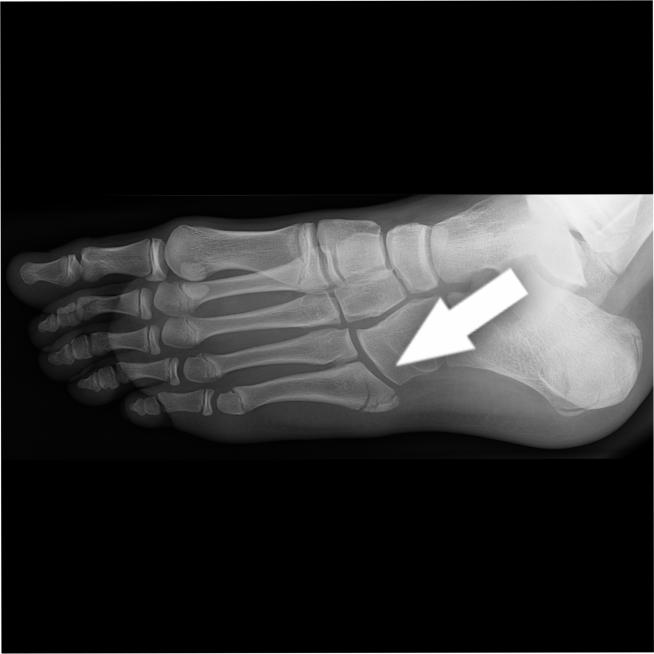

A base of 5th Metatarsal (MT) Fracture occurs at the base of the bone on the outside of the foot. It can happen when you twist your foot. You may experience pain on the outside of the foot with difficulty weightbearing as well as bruising and swelling.

If you have the symptoms noted above, this will prompt the clinician to get an X-Ray of the foot that can show a break (fracture) in the base of the 5th MT.